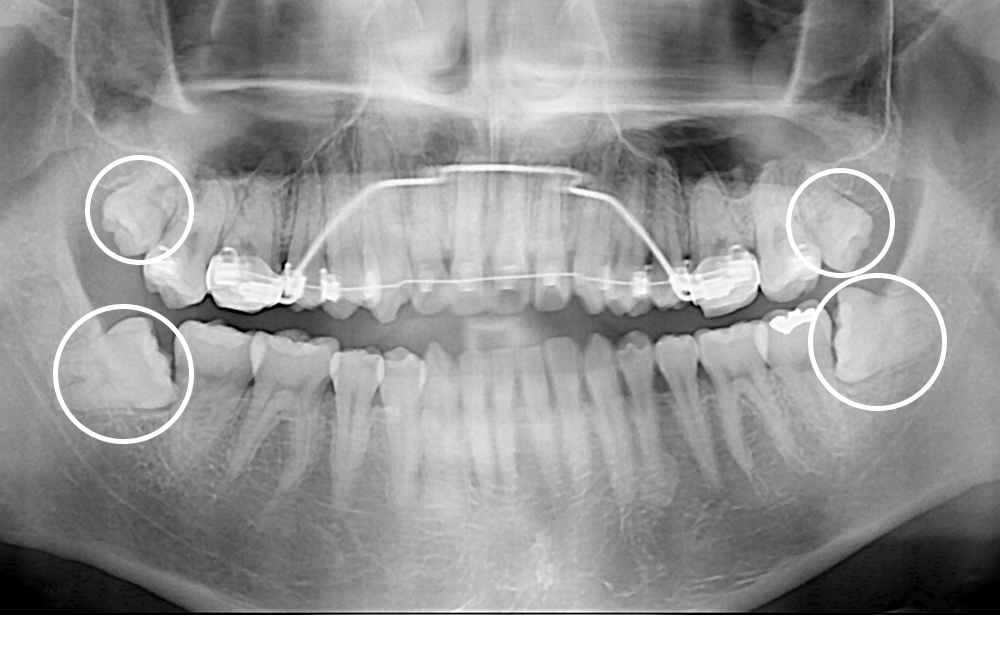

[사랑니] 매복 사랑니 발치

치료후 : 2016-03-12